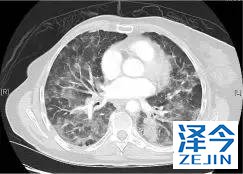

一位77岁的女性患有EPS15-NTRK1 IV期非小细胞肺癌,我们可以看到她的双肺满是病灶,并且出现了肝脏和脑转移,可以说是非常非常晚期了,

开始使用larotrectinib 100 mg BID并持续治疗,

第3周期开始:

肺靶病变达到缓解,我们可以明显的看到前后的图像,病灶明显缩小了,

脑转移病变显示缩小了95%!

初始, 2018年6月 3周期 2018年8月